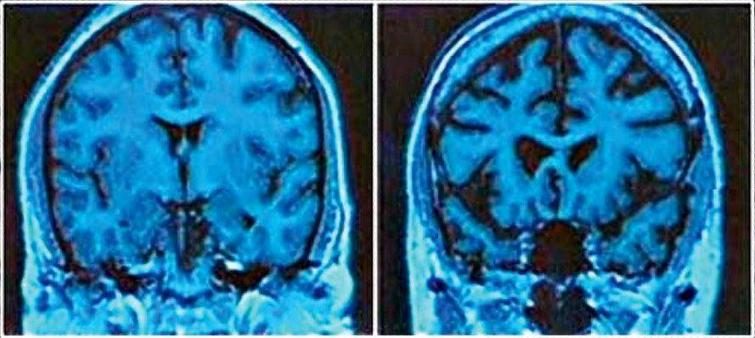

Слева — нормальный мозг 43-летнего человека, справа — мозг 43-летнего алкоголика